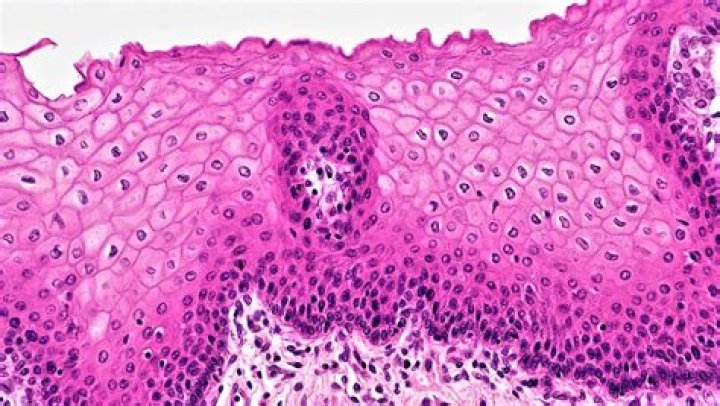

Does stratified squamous epithelium have cilia?

What is a stratified squamous epithelium?

Stratified squamous epithelia have two or more layers of cells, with a superficial squamous layer and basal layers that are usually cuboidal or columnar. ... This type of epithelium can withstand abrasion because the loss of cells from the surface does not compromise the underlying tissue.

How do you identify stratified squamous epithelium?

When classifying a stratified epithelial sheet, the sheet is named for the shape of the cells in its most superficial layers. So a stratified squamous epithelium only necessarily has squamous-shaped cells in its highest layers and might have a different-shaped cell in its lower layers.